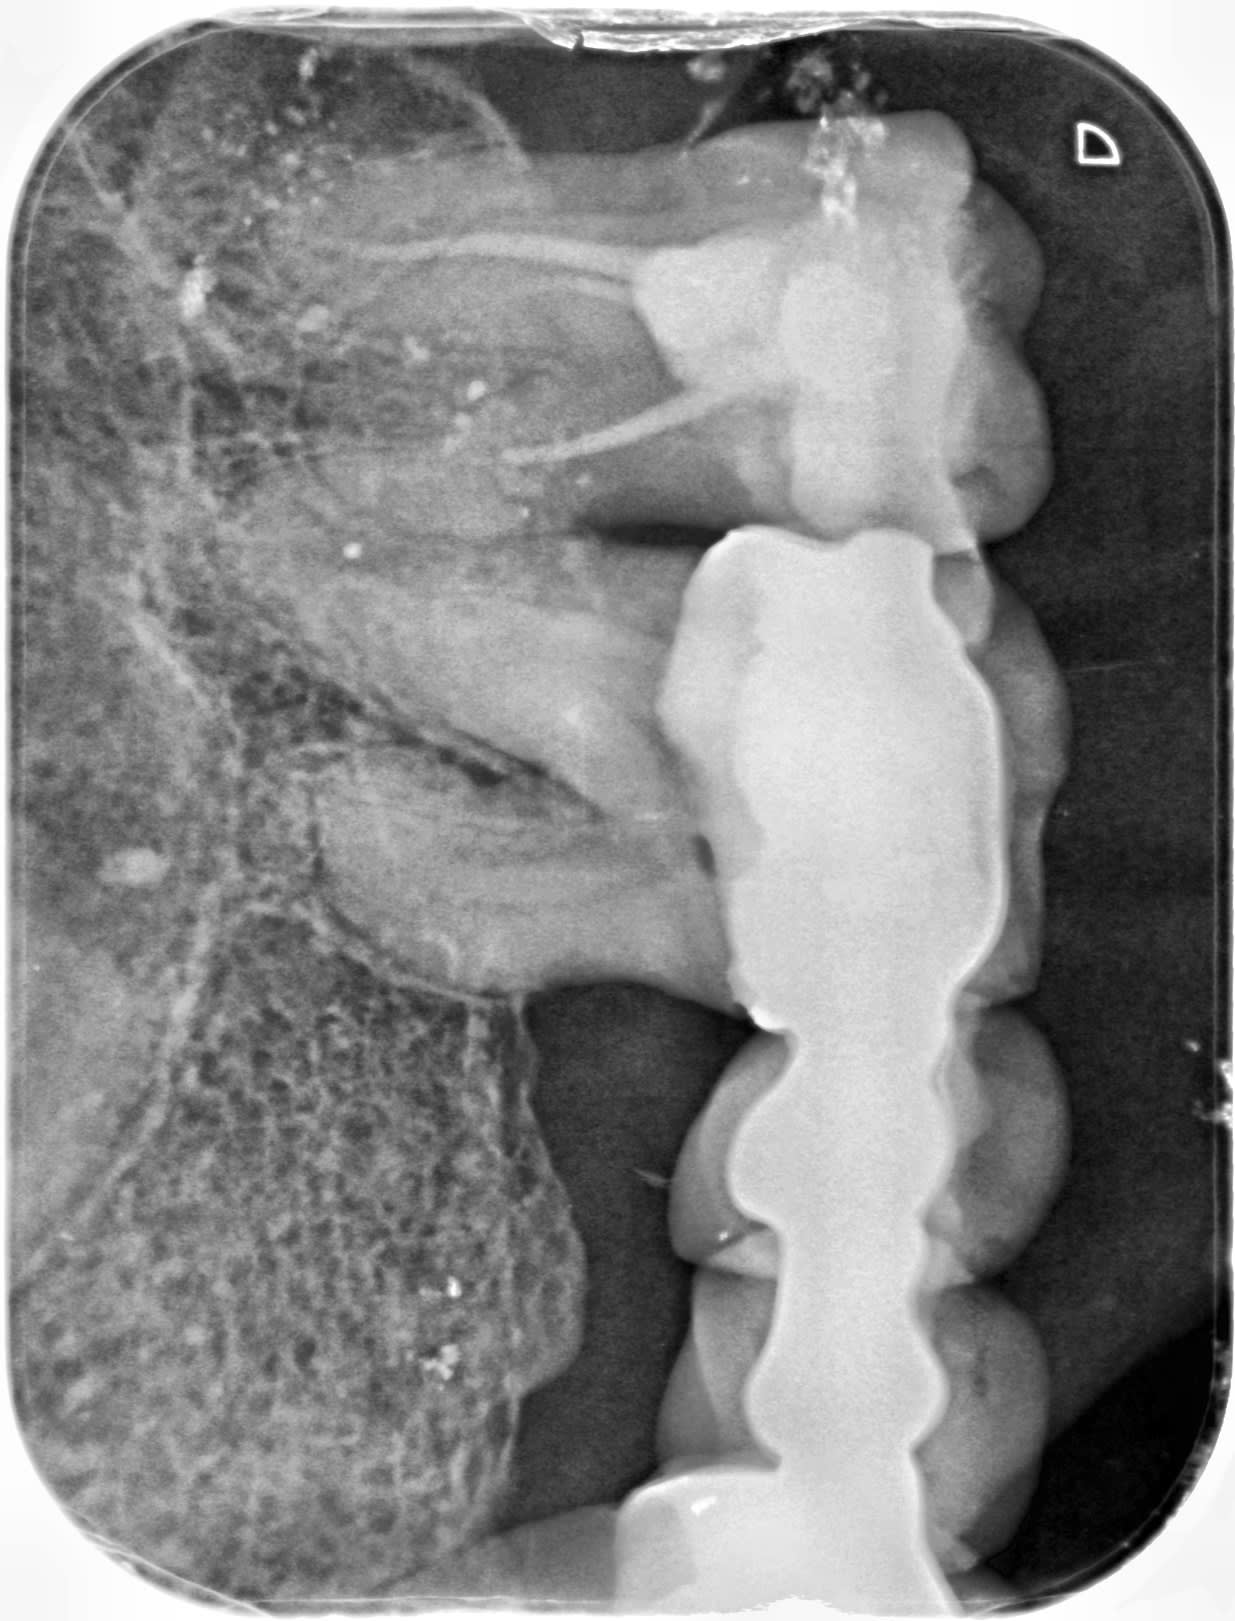

donc là j'avais fait une pulpo sur la 26,

pour me rendre compte que la dent causale était la 27 que j'ai extraite par la suite

malgré des entrés canalaires évidentes la prise de LO est une catastrophe.

à la première radio je pense quez je suis bien sur le DV et mauvais sur le palatin alors que c' est l'inverse

puis j’enchaîne les reprises , recherche de mv ( 1 ou 2) , je m'enfonce et n'arrive plus , ne comprends pas comment je peux retrouver le DV.